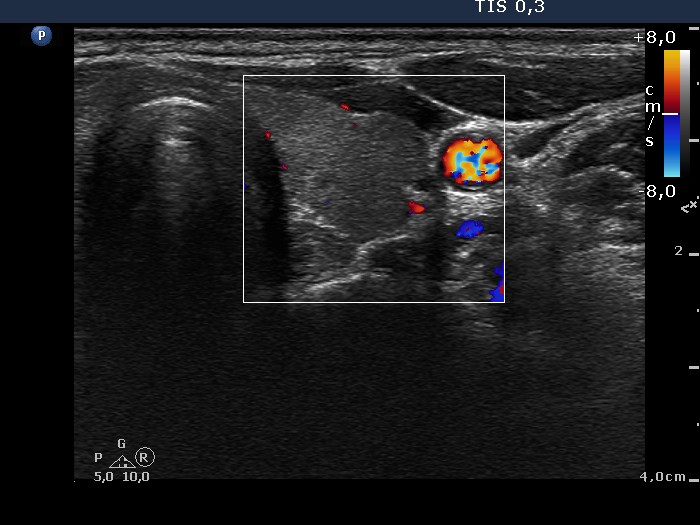

Chronic lymphocytic thyroiditis - Case 33.

Follow-up investigation 2 years later

(ultrasonographic picture 6)

Left lobe, horizontal scan, color Doppler mode. The thyroid is avascular.